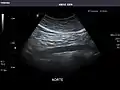

Aorta

Aorta: Visualized portions normal in caliber, 16 x 15 mm.

It can be used on the abdominal aorta to detect or exclude abdominal aortic aneurysm. For this purpose, the standard aortic measurement for abdominal aortic aneurysm is between the outer margins of the aortic wall.[4]